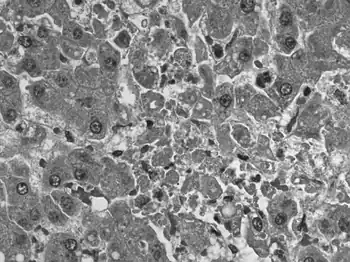

| Negative stain electron micrograph of an arenavirus from a mouse that tested positive for LCM | |